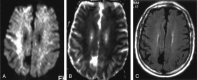

F<sc>ig</sc> 2.

Fig 2.

Isolated restricted diffusion in a patient who recovered without residual symptoms. A, DW image shows asymmetric (right greater than left) high signal intensity in the superior corona radiata and subcortical white matter. B, Corresponding ADC map shows subtle low signal intensity. C, No abnormalities are present on the FLAIR image.